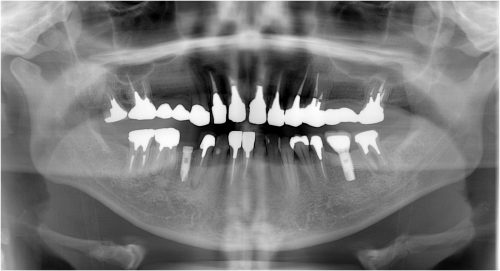

歯髄壊死 左上の前歯 川口の歯科 歯医者 さかえ歯科クリニック

2014年12月16日